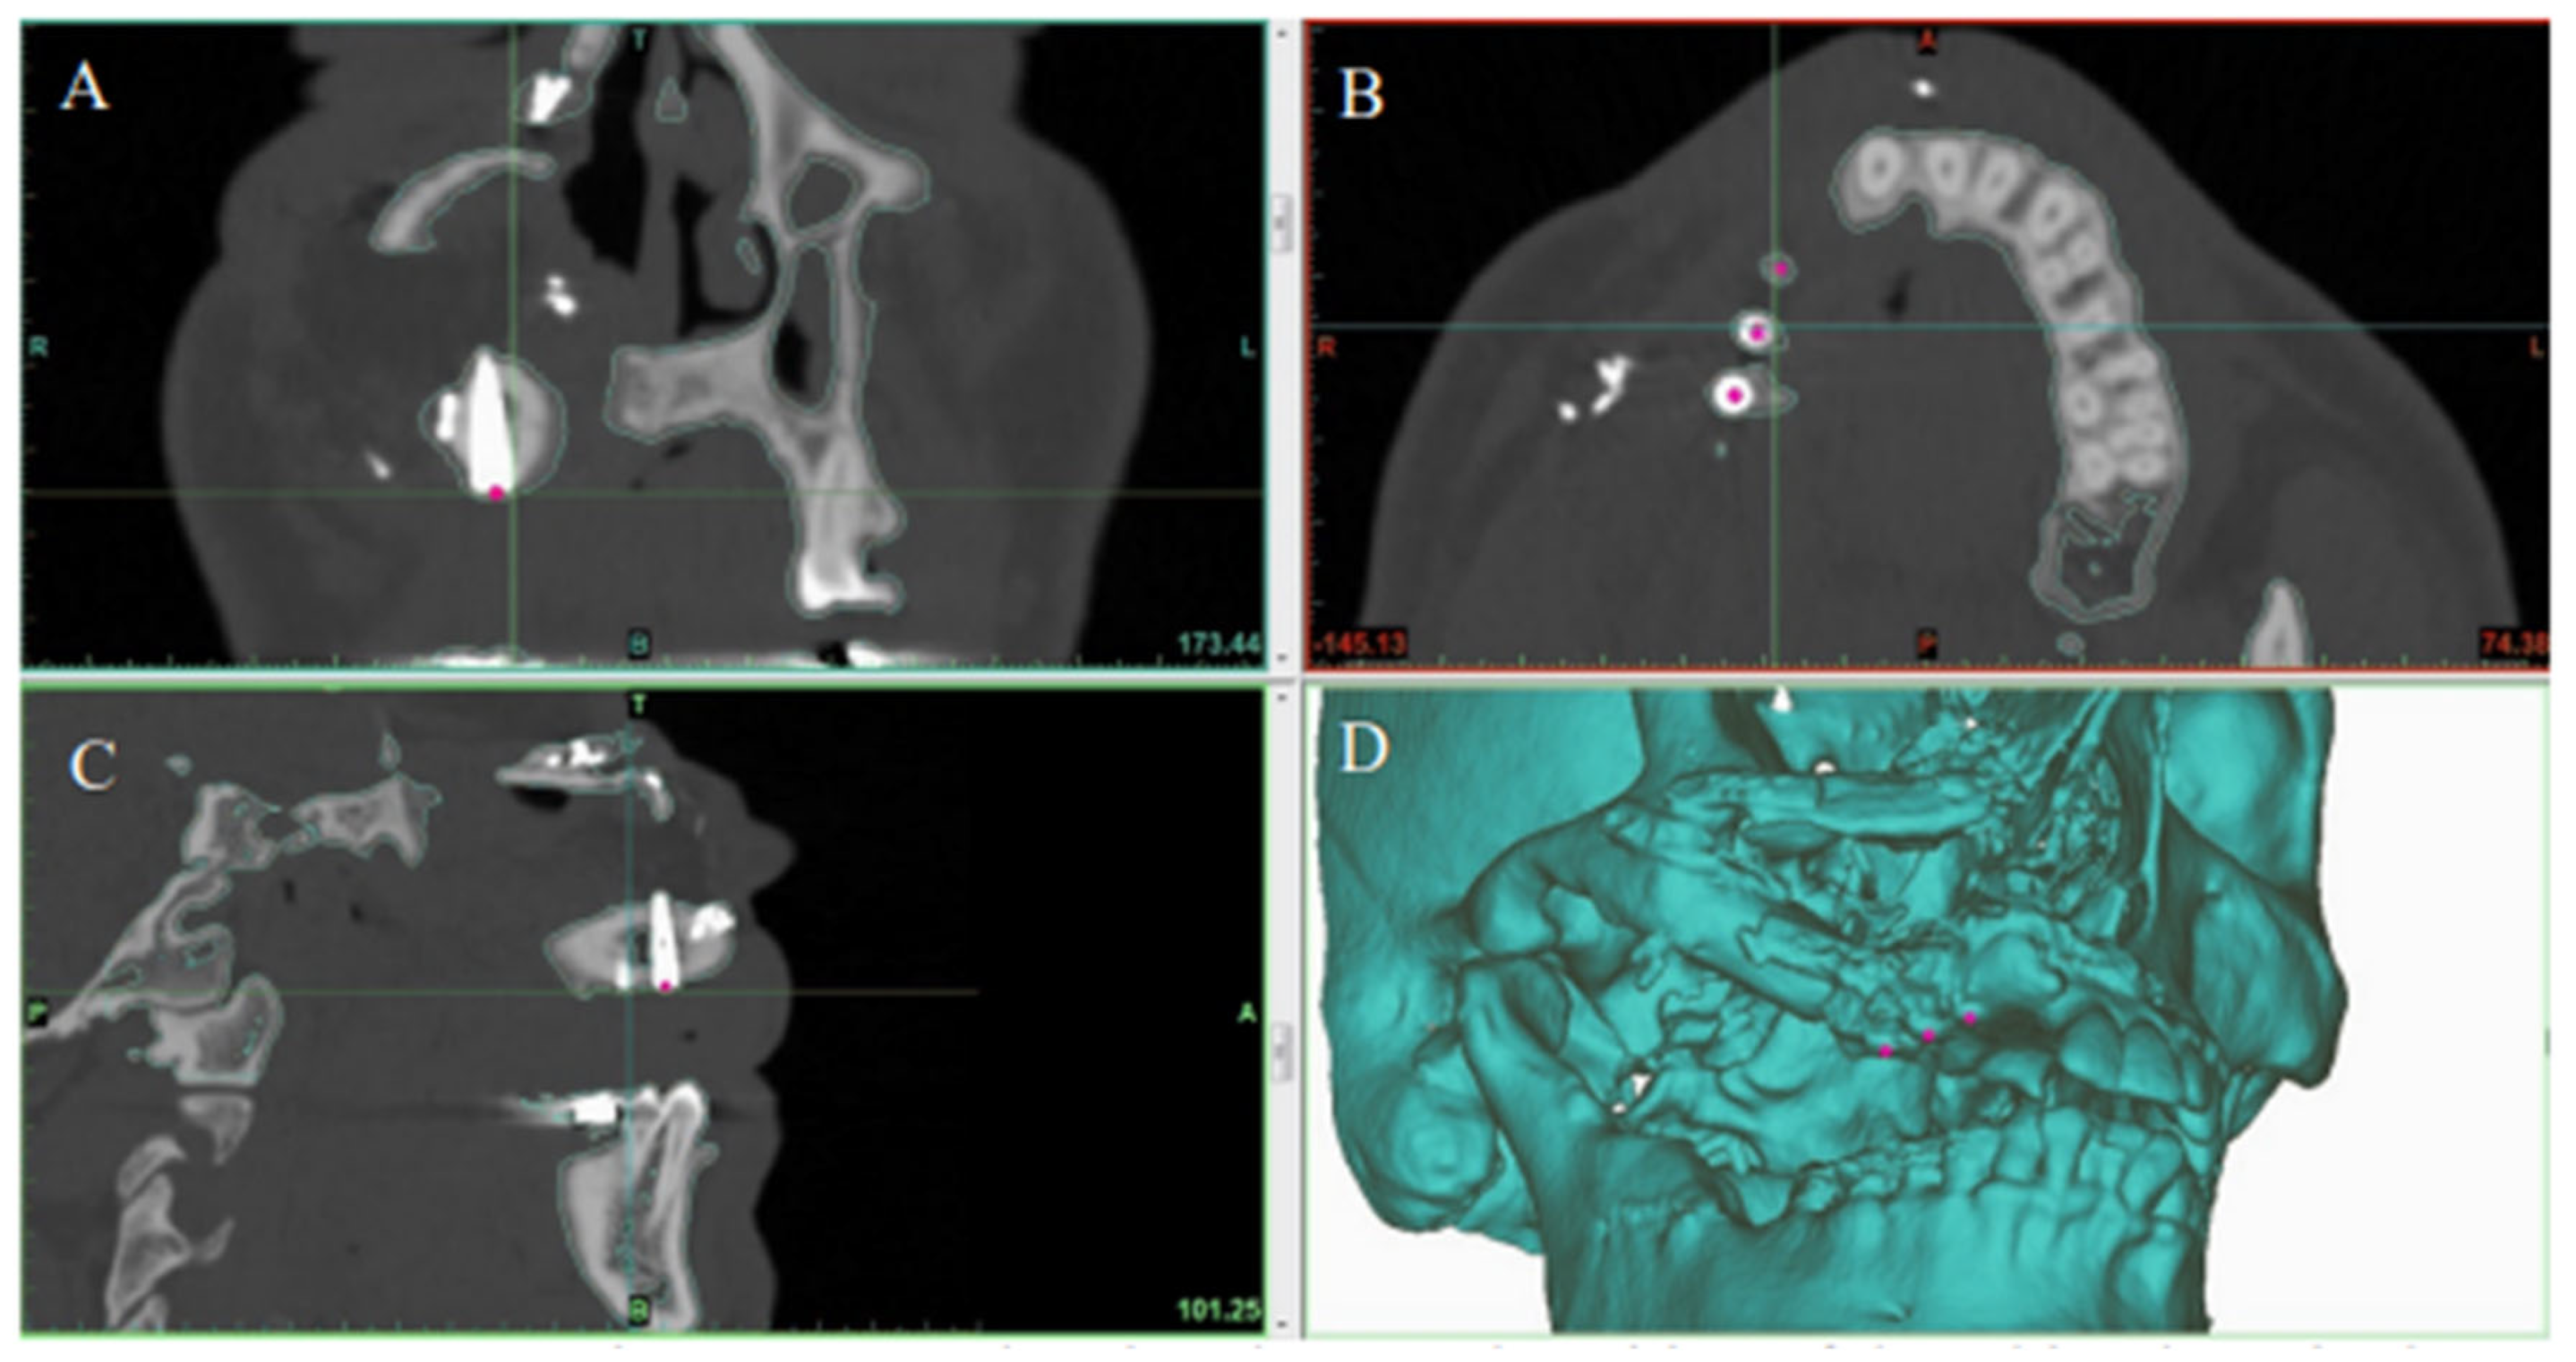

The primary outcome of this study was the accuracy of the postoperative implant positions as compared to the SDS plan. Each patient had a high-resolution helical CT scan of the facial bones using either a Somatom Sensation (Siemens, Germany) or a GE VCT (GE Healthcare, Waukesha, WI) 64-slice CT select scanner via a 0.625 mm collimation with a 25.0 cm field of view and 0 degree gantry tilt. All patients had postoperative CT scans of their facial bones 6–12 months after the Stage II procedure.

2.6. Data Analysis

The preoperative digital plan, referred to as “planned”, and the scans of the postoperative results, referred to as “actual”, were used for our analysis. Digitally placed spheres (1 mm diameter) were manually positioned in the geometric center of the planned and actual implant positions along the occlusal surface of the fibula. The spheres defined the reference point for measuring implant position. The X, Y, and Z coordinates of each planned and actual implant position were obtained (Figure 5 and Figure 6). The difference in position of the dental implants between the preoperative planned and postoperative actual CT scans was calculated in millimeters.

Figure 5. Preoperative CT scan showing virtual planned placement of dental implants in the reconstructed jaw in the (A) coronal, (B) axial, and (C) sagittal planes. (D) 3D model showing the final jaw reconstruction with implants in the ideal position according to virtual surgical plan.